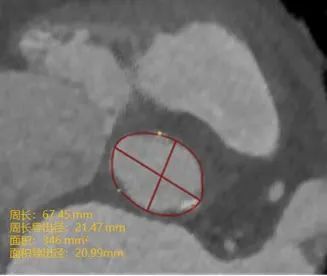

高年资医生定位测量瓣环的结果

人工智能定位测量瓣环的结果